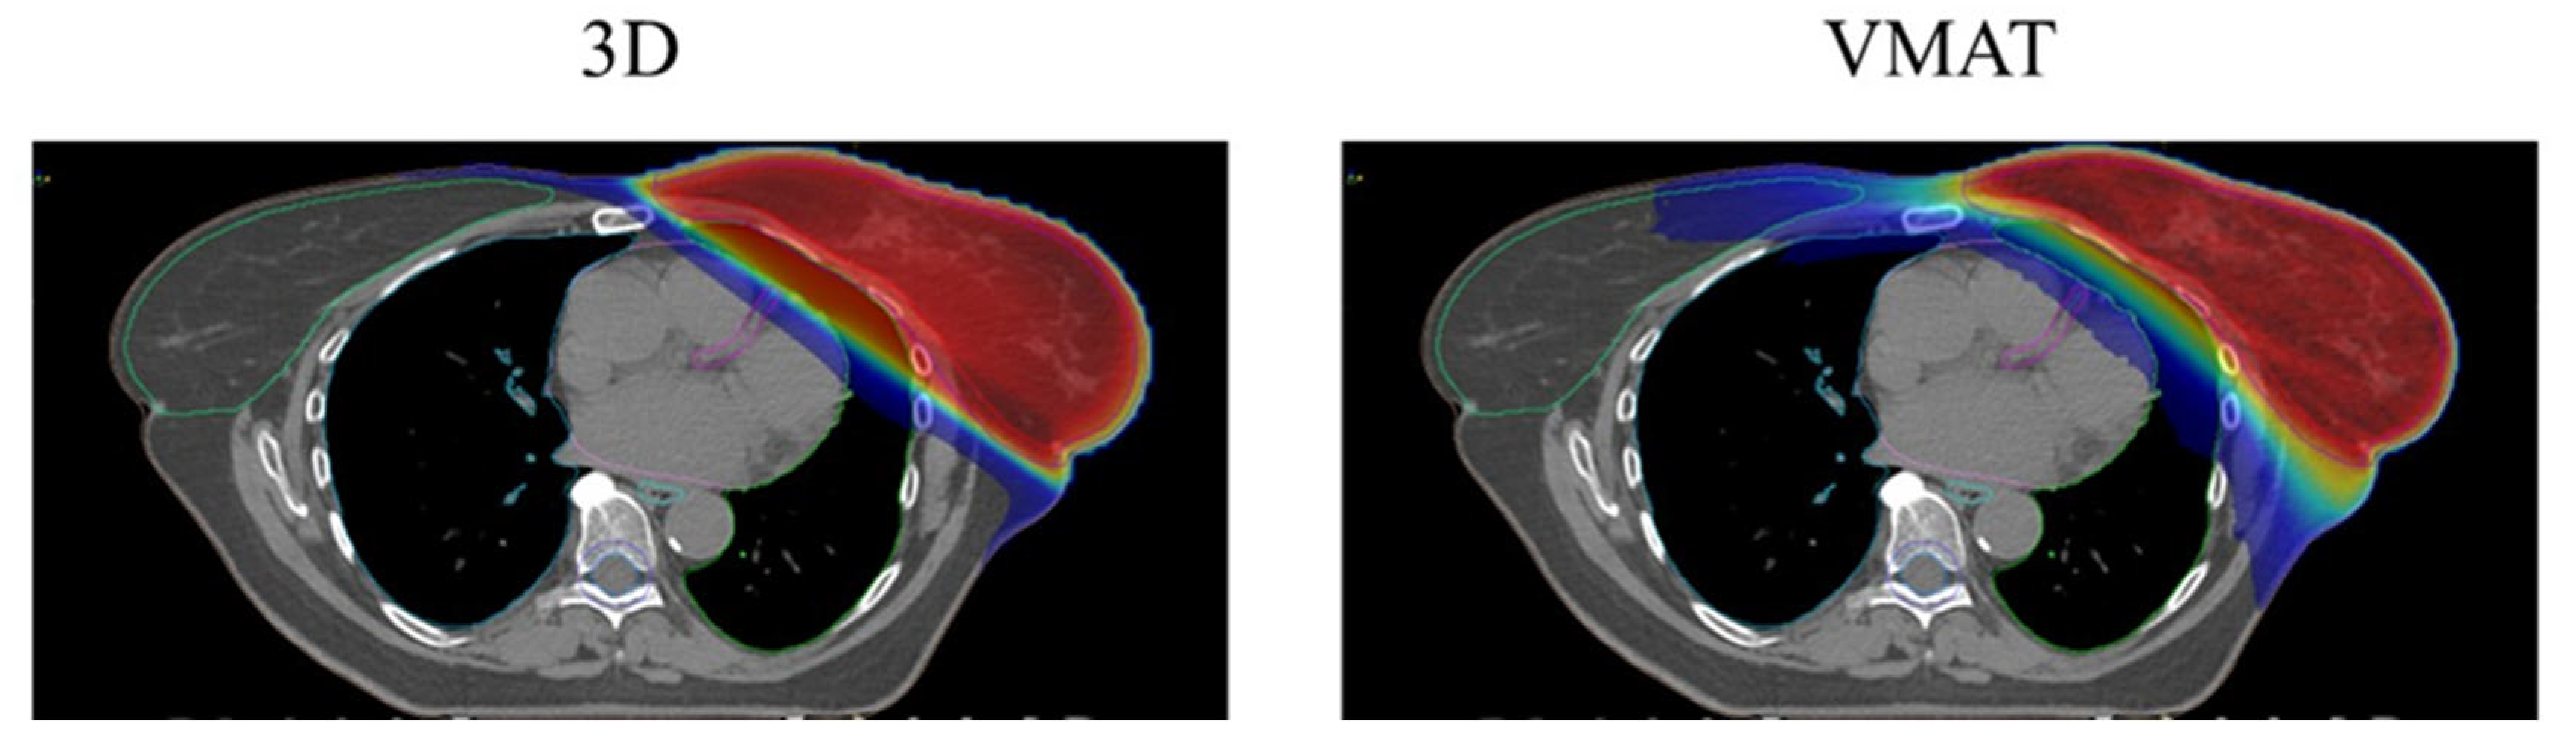

The choice of irradiation technique often lies between two options: 3D conformal radiation therapy (3DCRT) or IMRT/volumetric arc-modulated radiation therapy (VMAT).

Donovan et al. [61] investigated the effects of WBI in a cohort of 360 patients, who were randomized to receive either conformal RT or IMRT. The study revealed that changes in breast appearance were 1.7 times more likely to be reported in the 3DCRT arm compared with IMRT (p = 0.008). Furthermore, IMRT significantly reduced the incidence of palpable induration, indicating its potential advantage in preserving cosmetic outcomes. Hörner-Rieber et al. [62] conducted a prospective, multicenter, randomized phase III trial comparing 3DCRT and IMRT for BC irradiation. A total of 502 patients were randomized, and after a median follow-up of 5.1 years, no significant differences were observed in disease control, late toxicities, or cosmetic outcomes. Mukesh et al. [63] randomized 815 BC patients to receive 40 Gy in 15 fractions delivered via 3DCRT versus IMRT. The primary endpoints were late cosmetic and breast toxicity outcomes. IMRT demonstrated fewer instances of suboptimal cosmesis (p = 0.027) and skin telangiectasia (p = 0.021) in univariate analysis. These findings were consistent in multivariate analysis for both outcomes (p = 0.038 and p = 0.031, respectively).

As shown in Figure 3, achieving optimal treatment target conformity and uniform dose distribution with 3DCRT can be challenging, often resulting in higher maximum doses to small sections of organs at risk (OARs) such as the heart and lungs [64]. IMRT and VMAT offer improved conformity and dose distribution, but they can increase low-dose radiation exposure to OARs, including the heart, lungs, and contralateral breast. Additionally, IMRT and VMAT require greater expertise and increased monitor unit usage from the linear accelerator, which may lead to higher resource consumption [65].

Figure 3.

Dose distribution: 3D versus VMAT.

Non-modifiable risk factors such as age and breast volume consistently emerge as significant contributors to late breast toxicity. Older patients frequently develop higher rates of fibrosis and breast edema, compromising both aesthetic and functional outcomes [20,21], while larger breast volumes introduce challenges due to dose inhomogeneity, leading to increased toxicity risks [25,26]. These findings emphasize the need for individualized radiation plans that consider unique anatomical and physiological characteristics, ensuring optimal and patient-specific care. A key focus of this review is on modifiable factors that can mitigate late breast toxicity. Among these, the selection of radiation dose and fractionation schedules is particularly influential. Hypofractionation, which administers higher doses over fewer sessions, has demonstrated efficacy in reducing toxicity without compromising therapeutic outcomes, establishing its value in modern radiotherapy [42,43,44,45]. Advanced irradiation techniques such as IMRT and VMAT further enhance therapeutic outcomes by improving dose homogeneity and minimizing radiation exposure to surrounding healthy tissues [61,62,63]. Despite the resource demands associated with these technologies, their benefits in reducing late toxicities and improving cosmetic results are well documented [64].